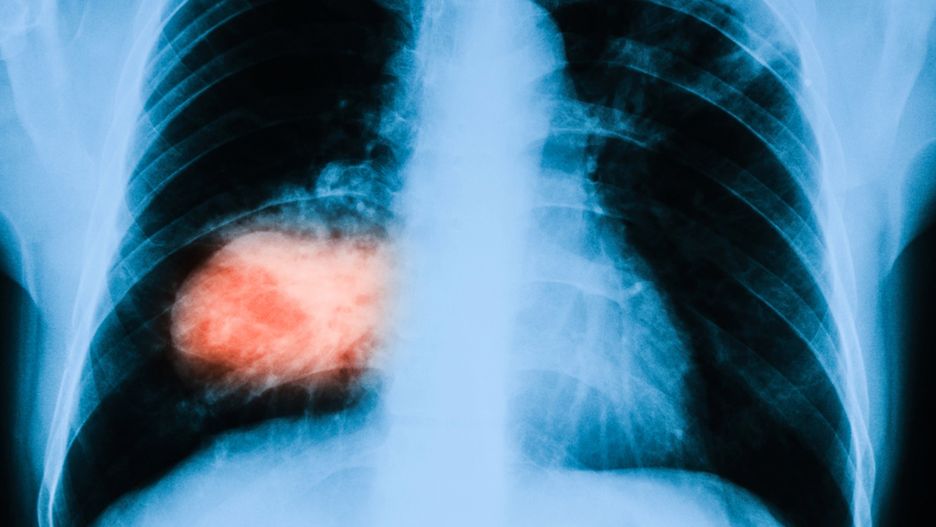

Pacjenci z nowotworem płuc nie skorzystają w nowoczesnego leczenia.

Pacjenci z nowotworem płuc nie skorzystają w nowoczesnego leczenia jaką jest immunoterapia. To metoda refundowana w większości krajów europejskich, m.in. na Słowacji, Węgrzech i w Rumunii. Indywidualny koszt leczenia to 20 tys. złotych miesięcznie. - Sami nie udźwigniemy takiej kwoty -skarżą się chorzy.

Rak płuca nadal jest na pierwszym miejscu wśród nowotworów złośliwych prowadzących do śmierci w Polsce. Wciąż umiera na niego więcej pacjentów niż na raka piersi, jelita grubego i prostaty łącznie. Na świecie, dzięki nowoczesnym metodom leczenia raka płuc, nowotwór ten zaczął być traktowany jak choroba przewlekła. - Niestety w Polsce na nowoczesne terapie mogą liczyć tylko pacjenci z rakiem piersi, jelita grubego czy czerniakiem - komentowała dla RMF 24 Anna Żyłowska ze Stowarzyszenia na Rzecz Walki z Rakiem. - Pacjenci z rakiem płuca traktowani są jako chorzy drugiej kategorii.

Znane są już liczne przypadki pacjentów, którzy dzięki nowoczesnemu leczeniu latami żyją w bardzo dobrej kondycji, choć pierwotnie ich choroba była w bardzo zaawansowanym stadium.

- Niestety w Polsce na refundację nowoczesnych terapii czeka się za długo, a pacjenci muszą szukać badań klinicznych lub organizować zbiórki pieniędzy, żeby samodzielnie zakupić lek - skomentowała Anna Żyłowska. - Odnoszę wrażenie, że państwo polskie chce, aby Polacy z własnych środków leczyli nie tylko grypę, ale i raka płuca - dodała.